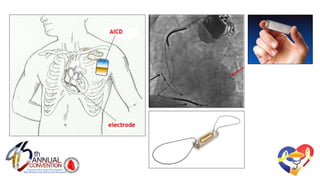

Clinical Cardiac Pacing, Defibrillation and Resynchronization

Therapy (4th ed). Ellenbogen et al. p. 261